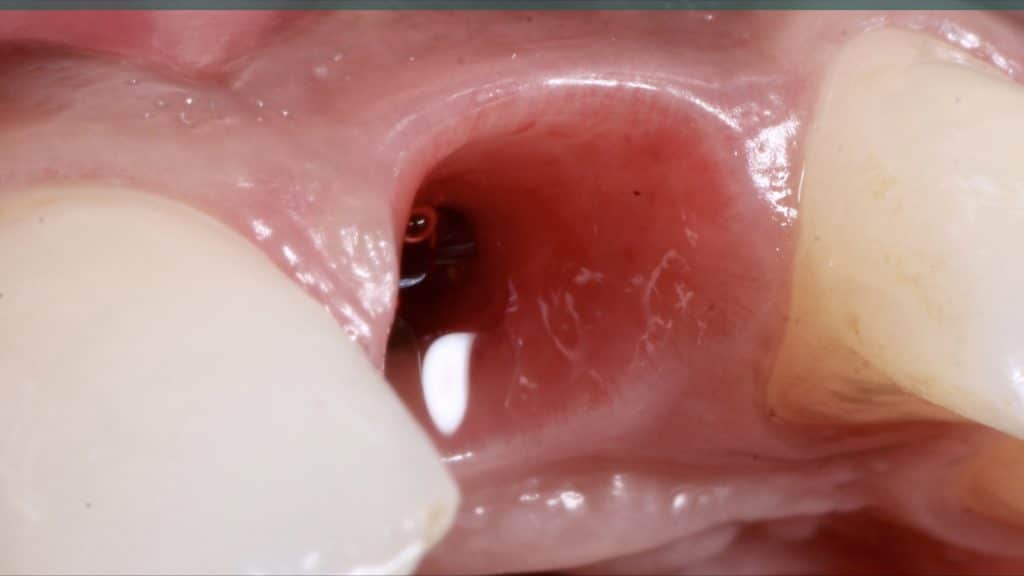

Immediate post-op